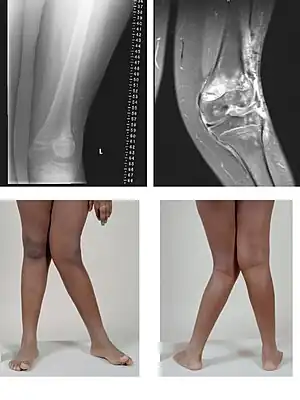

| Valgus deformity of the knee (genu valgum), seen in MRI and photograph | |

A valgus deformity is a condition in which the bone segment distal to a joint is angled outward, that is, angled laterally, away from the body's midline.[1] The opposite deformation, where the twist or angulation is directed medially, toward the center of the body, is called varus. Common causes of valgus knee (genu valgum or "knock-knee") in adults include arthritis of the knee and traumatic injuries.

- Knee: genu valgum (from Latin genu = knee) – the tibia is turned outward in relation to the femur, resulting in a knock-kneed appearance.

Knee arthritis with valgus knee

Rheumatoid knee commonly presents as valgus knee. Osteoarthritis knee may also sometimes present with valgus deformity though varus deformity is common. Total knee arthroplasty (TKA) to correct valgus deformity is surgically difficult and requires specialized implants called constrained condylar knees.